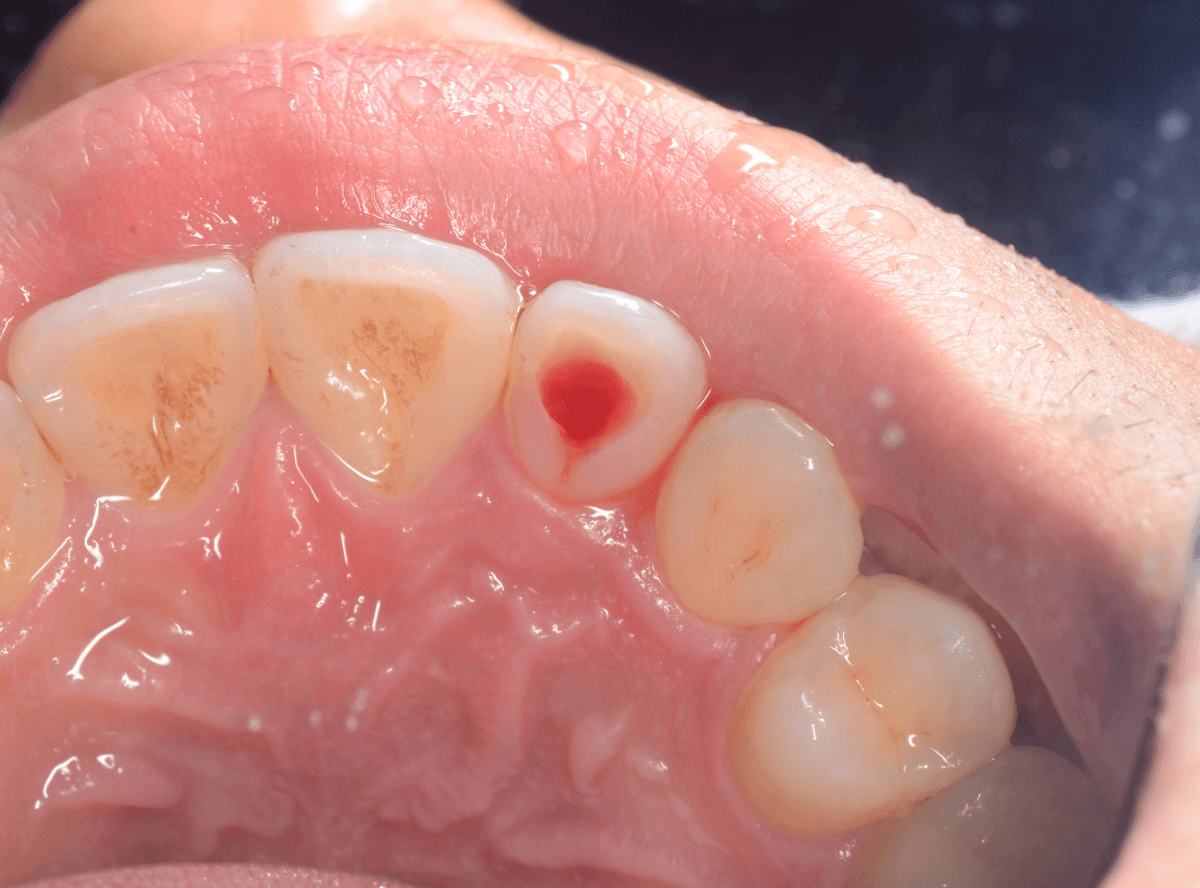

出血が止まったのを確認して、お薬を出して当日は治療終了です。

炎症がぶりかえして、痛みが再発するのを防止するために、歯の裏の穴は数日間開けっぱなしにします。

歯の中のガスは逃げていきますが、外からもバイ菌が入ってきますので、症状が抜けたら短期間で穴をふさぐ必要があります。